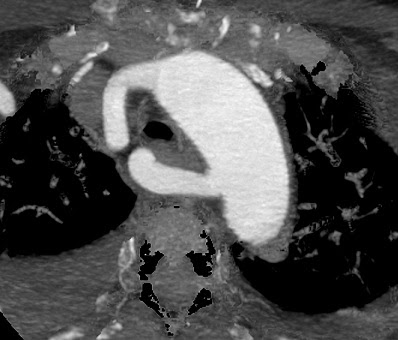

caso 3

Paciente

de 68 años de edad con ictus isquémico múltiple en territorio

vertebrobasilar, dudosa estenosis vertebral derecha.

Diagnóstico:

Arteria subclavia derecha aberrante.